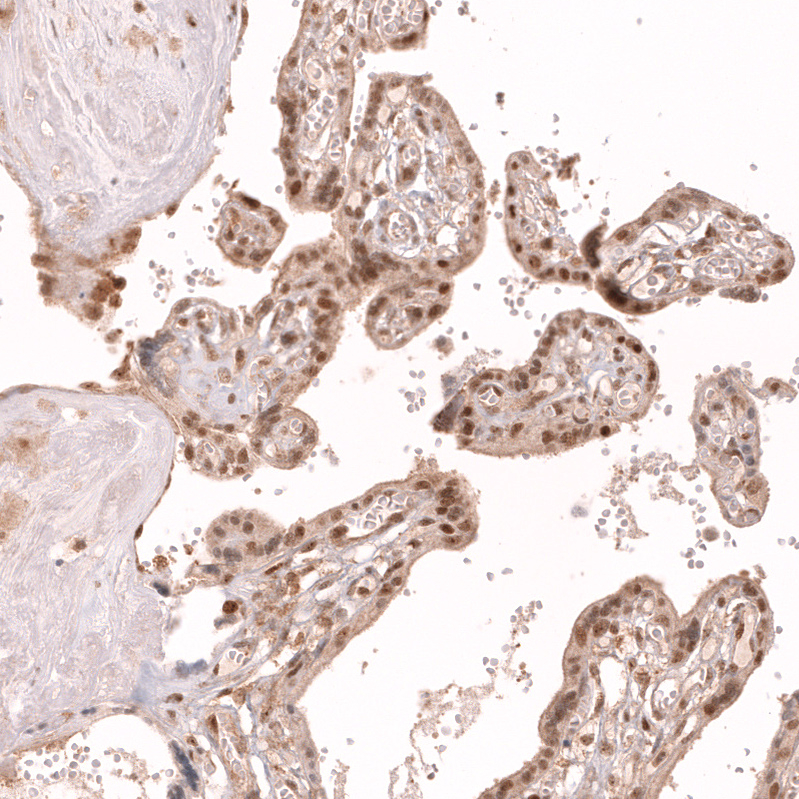

Immunohistochemistry analysis in human tonsil and liver tissues using AMAb91946 antibody. Corresponding TFEB RNA-seq data are presented for the same tissues.